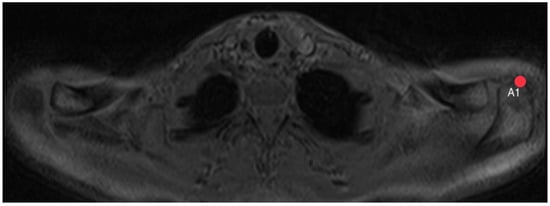

2.3. Acromion Index (Figure 1)